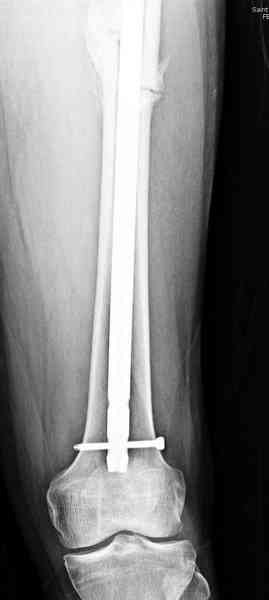

В первый же день произведено антеградное штифтованием DePuy Trochanteric Nail.

и проведены шурурпы через и спереди штифта без удаления.

Послеоперационные снимки